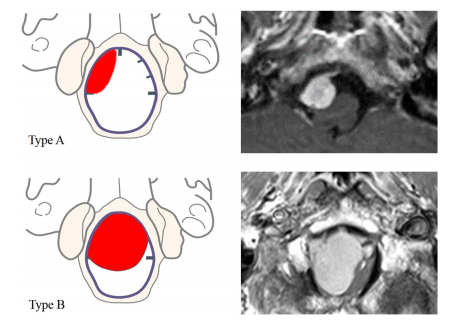

圖5(左)和T1加權(quán)磁共振圖像的兩個(gè)治療病例(右)顯示的例子,兩個(gè)不同的軸向平面位置的腫瘤。完全在一側(cè),沒(méi)有超出中線的延伸(A型)和中線兩側(cè)的硬腦膜附著物(B型)